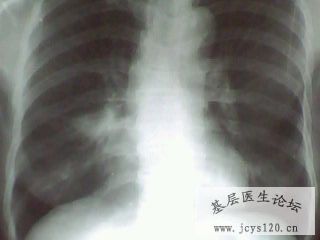

患者胸痛5天体温正常 咳嗽时疼痛加重既往体健 阅读全文>